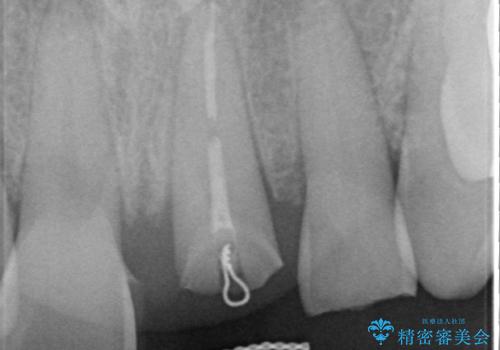

左上1が水平的に割れている状態で、歯冠を取り除くと神経が露出しており、唇側はかなり歯肉縁下で破折しており、そのままではかぶせものを入れるのは難しい状態でした。

根管治療をした上で歯を引っ張りだして(エクストリュージョン)、その後、骨外科にて歯周組織を整えた上で、かぶせものを入れていく治療計画をたてました。